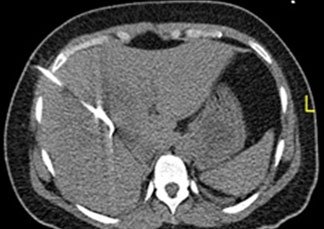

Ascites and Pleural fluid drainage

PCD in liver abcess